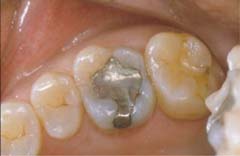

■ダイレクトボンディング■

施術前

施術後

ダイレクトボンディングとは、初期虫歯や小さな金属の再修復や変色した詰め物の再修復などに最適な治療方法です。

上記の写真は、最近ではほとんど見かけないアマルガムで治療されていました。(歯の変色や金属イオンの流出が体の健康を損なうと懸念されています。)

色調の改善だけではなく、歯が持つ本来の形態に修復し、咬む機能も同時に取り戻します。